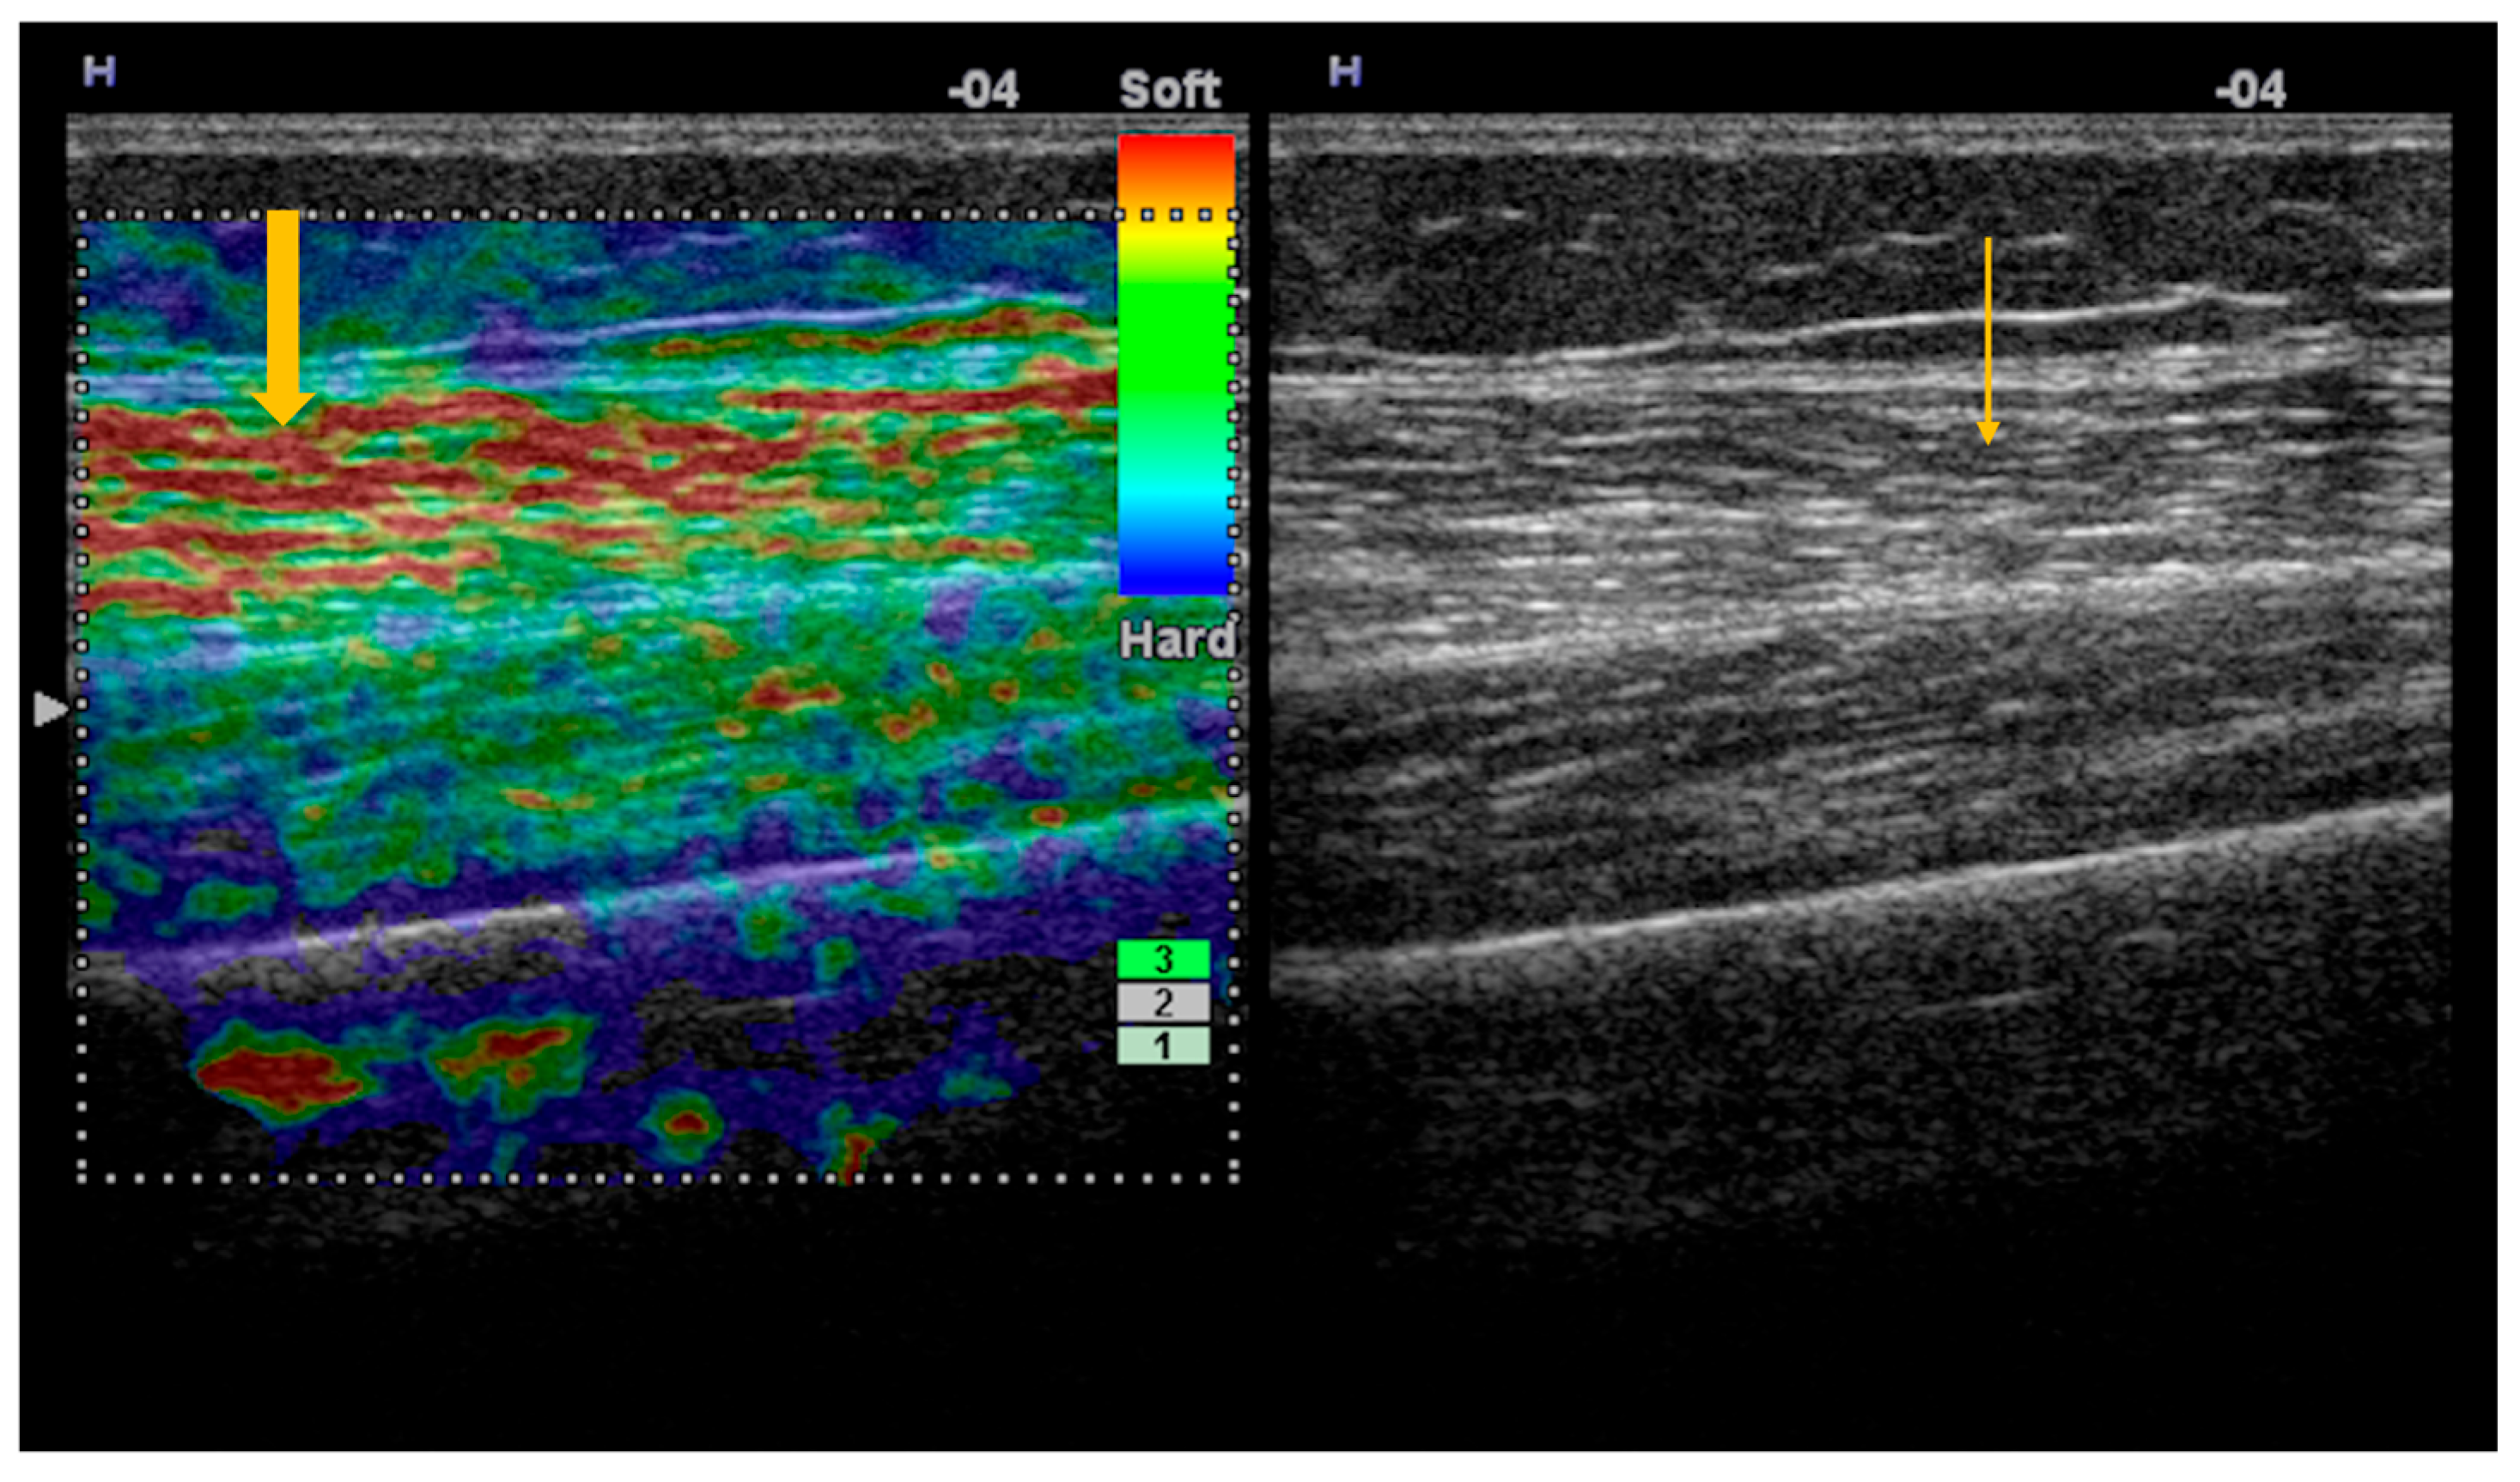

Elastography, both strain and shear-wave, provides additional information to conventional ultrasonography, demonstrating increased stiffness in the acute phase of myositis and reduced stiffness during disease progression, in the context of fatty infiltration (Figure 1) [35]. Because standardized reference values for normal muscle stiffness are not available in the literature, studies rely on comparisons between patients with Sjögren’s syndrome and healthy subjects. In patients with inclusion body myositis, muscle stiffness measured by shear-wave elastography (m/s) is lower compared with normal muscle: vastus lateralis (1.35 ± 0.32 vs. 1.68 ± 0.23), rectus femoris (1.52 ± 0.33 vs. 1.81 ± 0.23), vastus medialis (1.36 ± 0.16 vs. 1.60 ± 0.21) vastus intermedius (1.62 ± 0.49 vs. 1.86 ± 0.22), biceps femoris (1.30 ± 0.14 vs. 1.67 ± 0.20), semitendinosus (1.33 ± 0.31 vs. 1.66 ± 0.23), semimembranosus (1.36 ± 0.28 vs. 1.71 ± 0.18) (p < 0.05) [36].

Figure 1. Strain elastography and corresponding gray-scale imaging of myositis with fatty infiltration. Strain elastography of the thigh skeletal muscle demonstrates reduced tissue stiffness, as indicated by red color coding on the elastography map (thick arrow), indicating softening of the affected muscle. The corresponding gray-scale ultrasound image shows hyperechoic muscle texture (thin arrow), consistent with fatty infiltration.